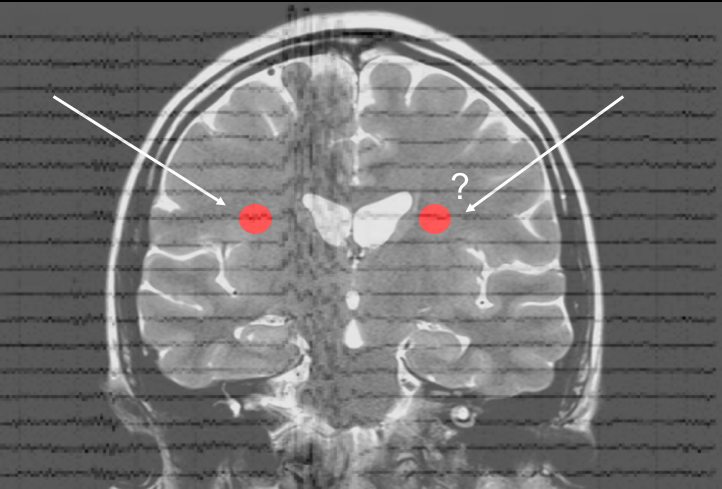

The figure below from [3] shows the localization of correlated sources from MEG data pertaining to simple auditory stimulation, in the left and right auditory cortex, where the dual source approach (shown in right) outperforms the traditional single-source LCMV beamformer (shown in left).

Figure 3: An example comparison of localization results using dual source and traditional LCMV beamformer.